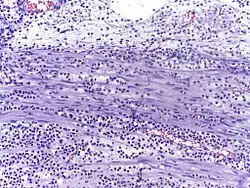

![]() |

Lepromatous leprosy | Skin biopsy showing epidermal atrophy and multiple dermal infiltrates. | Category: Histopathology of leprosy | Leprosy |